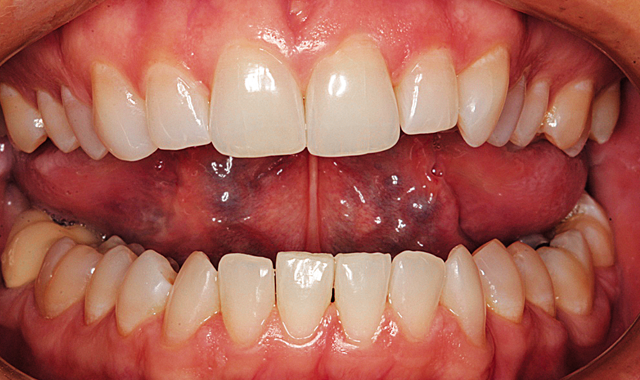

Mary presented with a desire to enhance her smile. Her main concern was the malalignment of her maxillary and mandibular anterior teeth. She was comfortable with the color of her teeth. Clinical and radiographic examination revealed excellent dental health, free of periodontal disease or caries.

Mary’s smile as she presented is shown in Figure 1. In the retracted view (Fig. 2) the malalignment is obvious. She was not concerned about the tipped maxillary premolars, but rather wanted to focus on the six anterior teeth.

Fig. 1

Fig. 2